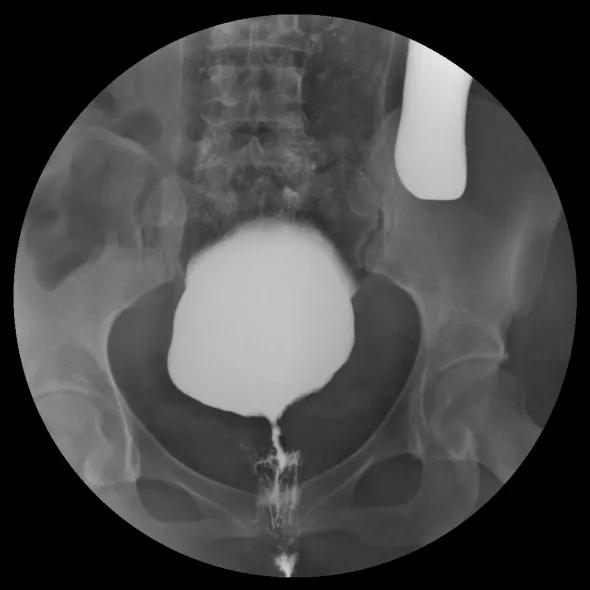

△直肠远端前壁→阴道内可见造影剂显示

小静不仅 直肠阴道瘘复发 了